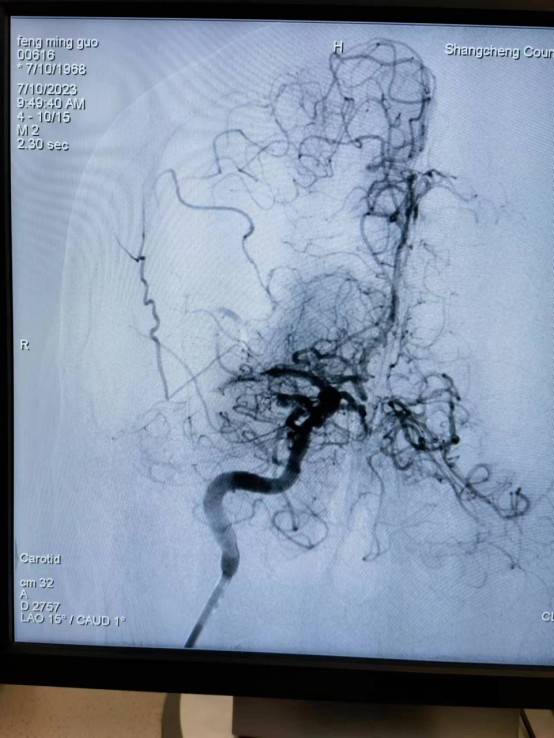

近日,55岁的冯先生突发急性脑梗死,我院卒中中心启动绿色通道,给予静脉溶栓桥接取栓治疗,成功打通堵塞的“生命管道”,患者转危为安,术后恢复良好,避免了“一人中风,全家瘫痪”的悲剧。

冯先生的成功救治,是静脉溶栓桥接动脉取栓治疗的完美结合。这次抢救工作的完美收官依靠的绝不仅仅是个人能力,它是整个团队共同努力的结果,检验了我院卒中中心对于脑卒中患者的快速鉴别诊断及多学科协作救治能力。我院卒中中心就是这样一支这样技术精湛、素质过硬的团队,在卒中介入治疗领域已经具备较强的综合实力,他们始终秉持着时间就是大脑、时间就是生命的理念,不断优化卒中急救模式和流程,为保障大别山区卒中患者能够得到及时、规范、有效的救治,降低县域卒中死亡率、致残率而不懈努力,为助力全面建设健康中国贡献自己的力量。